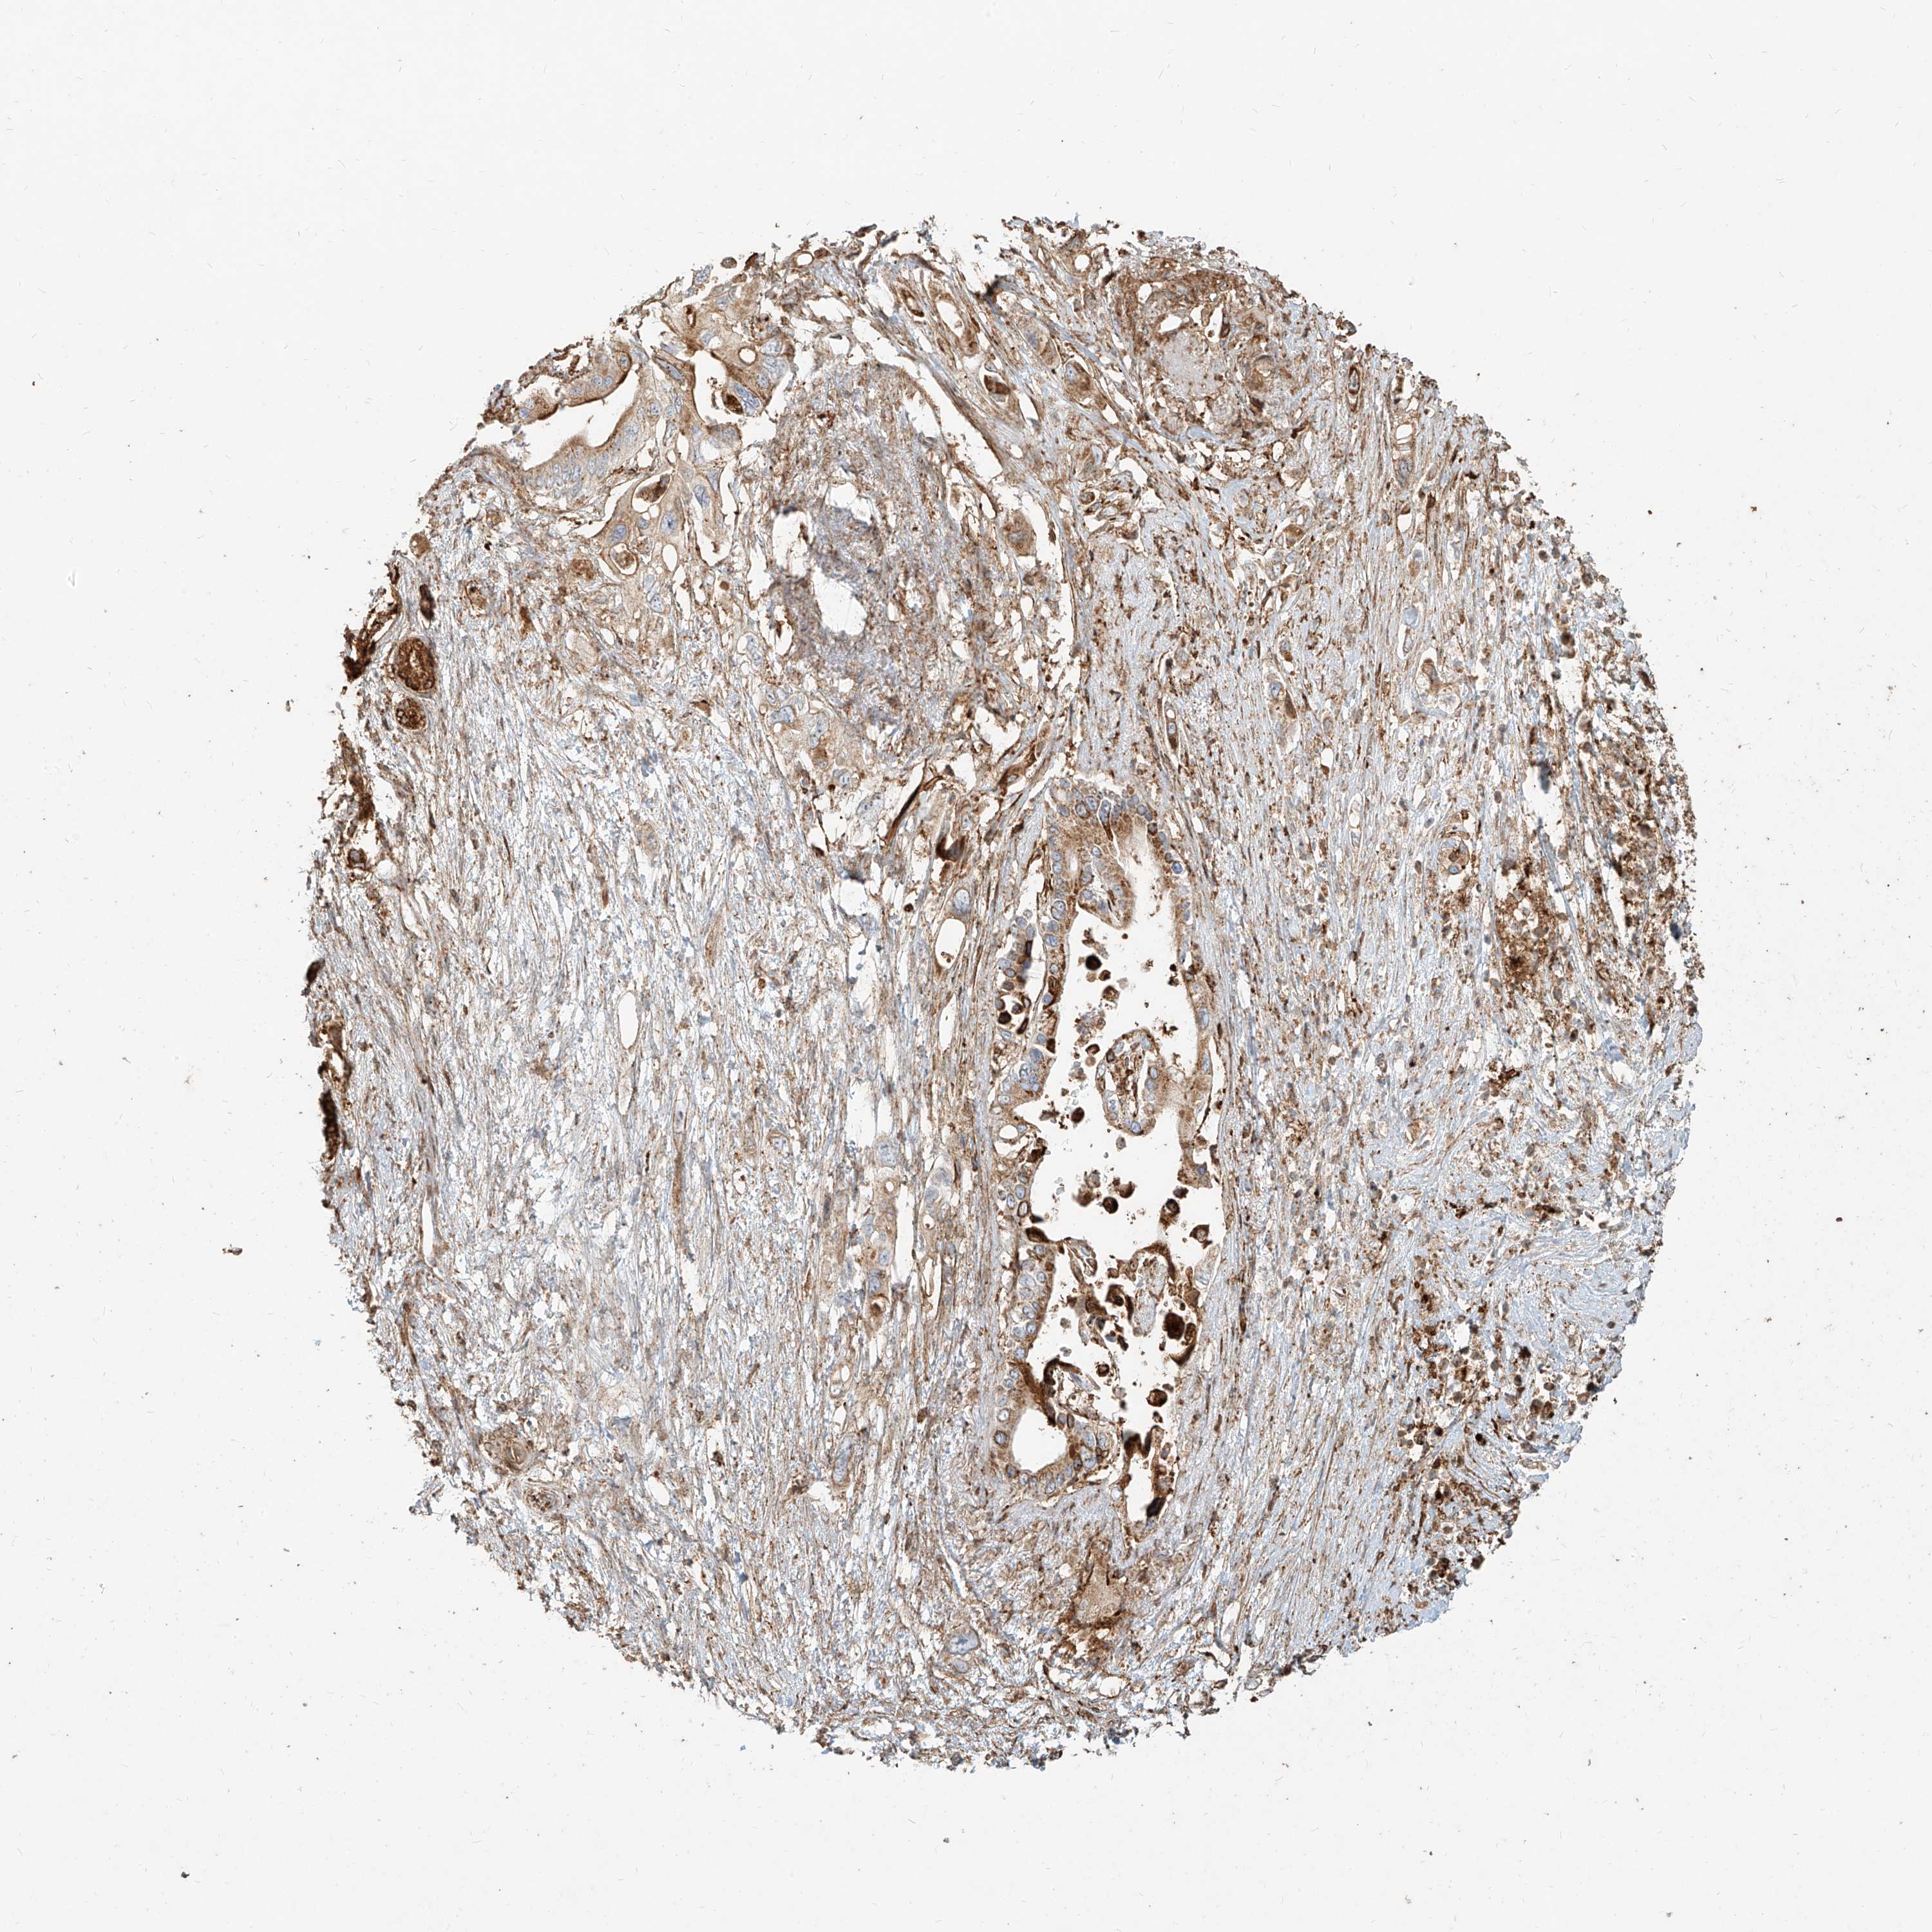

PANCREATIC CANCER - Protein expressioni

A mouse-over function shows sample information and annotation data. Click on an image to view it in a full screen mode. Samples can be filtered based on level of antibody staining by selecting one or several of the following categories: high, medium, low and not detected. The assay and annotation is described here.

Note that samples used for immunohistochemistry by the Human Protein Atlas do not correspond to samples in the TCGA dataset.

Antibody stainingi

Antibody staining in the annotated cell types in the current human tissue is reported as not detected, low, medium, or high, based on conventional immunohistochemistry profiling in selected tissues. This score is based on the combination of the staining intensity and fraction of stained cells.

Each image is clickable and will lead to virtual microscopy that enables deeper exploration of all samples and also displays staining intensity scores, fraction scores and subcellular localization as well as patient and tissue information for each sample.

Antibody HPA031550

Antibody HPA031551

Antibody HPA031552

Staining

High

Medium

Low

Not detected

Intensity

Strong

Moderate

Weak

Negative

Quantity

>75%

75%-25%

<25%

None

Location

Nuclear

Cytoplasmic/membranous

Cytoplasmic/membranous,nuclear

Adenocarcinoma, NOS